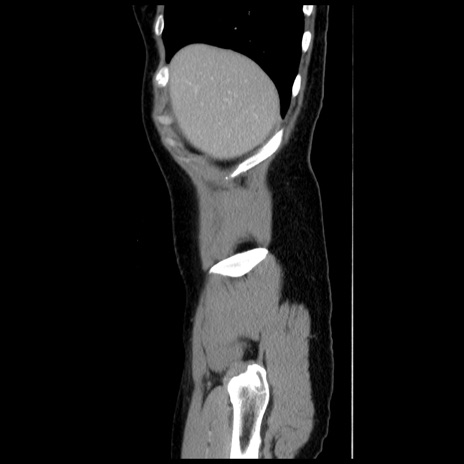

症例

【症例】 50歳代女性

【主訴】 腹痛

【現病歴】前日生レバーを食べた。今朝に排便あり。 昼前に突然発症の腹痛を生じ、当院救急外来を受診した。

【既往歴】 子宮筋腫にてで子宮全摘後

【身体所見】 意識清明、腹部:平坦、軟、下腹部やや左を中心に圧痛・反跳痛あり、筋性防御あり

【データ】WBC 7800、CRP 0.07